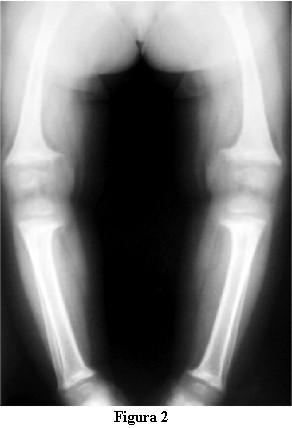

Las radiografías óseas mostraron una descalcificación global, los huesos largos incurvados y ensanchamiento de las metáfisis de los mismos en forma de copa (figuras 2 y 3).

En la evolución a los 3 meses de iniciado el tratamiento con calcitriol, a los 2 años y 9 meses, la marcha tiene las dificultades derivadas de las deformaciones de los miembros pero no presenta caídas, ni fatigabilidad, ni sudoración. La talla es de 81 cm , por debajo del percentil 3. La velocidad del crecimiento de los últimos 3 meses es de 8 cm/año. La fontanela anterior está completamente cerrada.Las radiografías óseas (figuras 4 y 5) muestran, a pesar del corto tiempo de evolución, una disminución del signo de la copa, con un progreso de la diáfisis hacia el tejido osteoide.